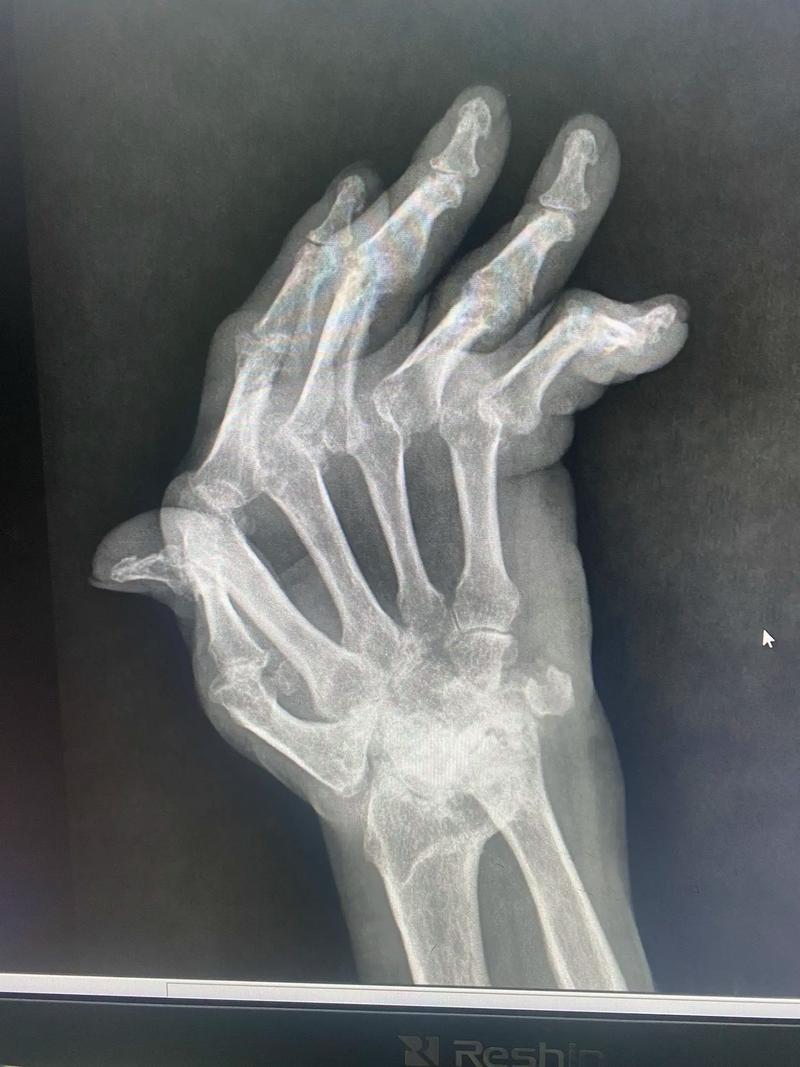

- 骨骼:直接侵蚀骨头,形成“骨侵蚀”或“骨质破坏”,在X光片上可以看到清晰的“虫蚀样”缺损。

当关节的软骨和骨骼被严重破坏,周围的韧带和肌腱也失去平衡时,关节就会失去正常的对位和功能,从而发生各种不可逆的畸形。

- 描述:这是手部RA最具标志性的畸形之一,当掌指关节(手指和手掌连接的关节)的结构被破坏后,手指会向小指(尺骨)一侧偏斜,像一把“军刀”的形状。